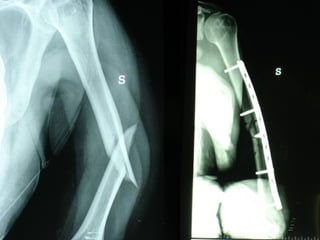

Dal Gennaio 2000 al Febbraio 2006 abbiamo trattato 167 fratture chiuse  con placca percutanea  in 164 pazienti :  27 lesioni diafisarie di gamba, 12 piloni tibiali ,  11 fratture prossimali di tibia, 36 fratture sovracondiloidee di femore, 17 fratture diafisarie di femore, 43 fratture metaepifisarie prossimali di omero, 21 diafisarie d’omero.  156 guarigioni 8 fallimenti

I buoni risultati ottenuti dipendono da 5 punti fondamentali:   una accurata riduzione percutanea della frattura  precise vie di accesso  l’utilizzo della placca che consenta il più lungo braccio di leva possibile il pretensionamento della placca  una sintesi con un ridotto numero di viti

Accurata riduzione percutanea della frattura

Precise vie di accesso

Placche lunghe e pretensionate

Placche lunghe e pretensionate Sintesi con un ridotto numero di viti